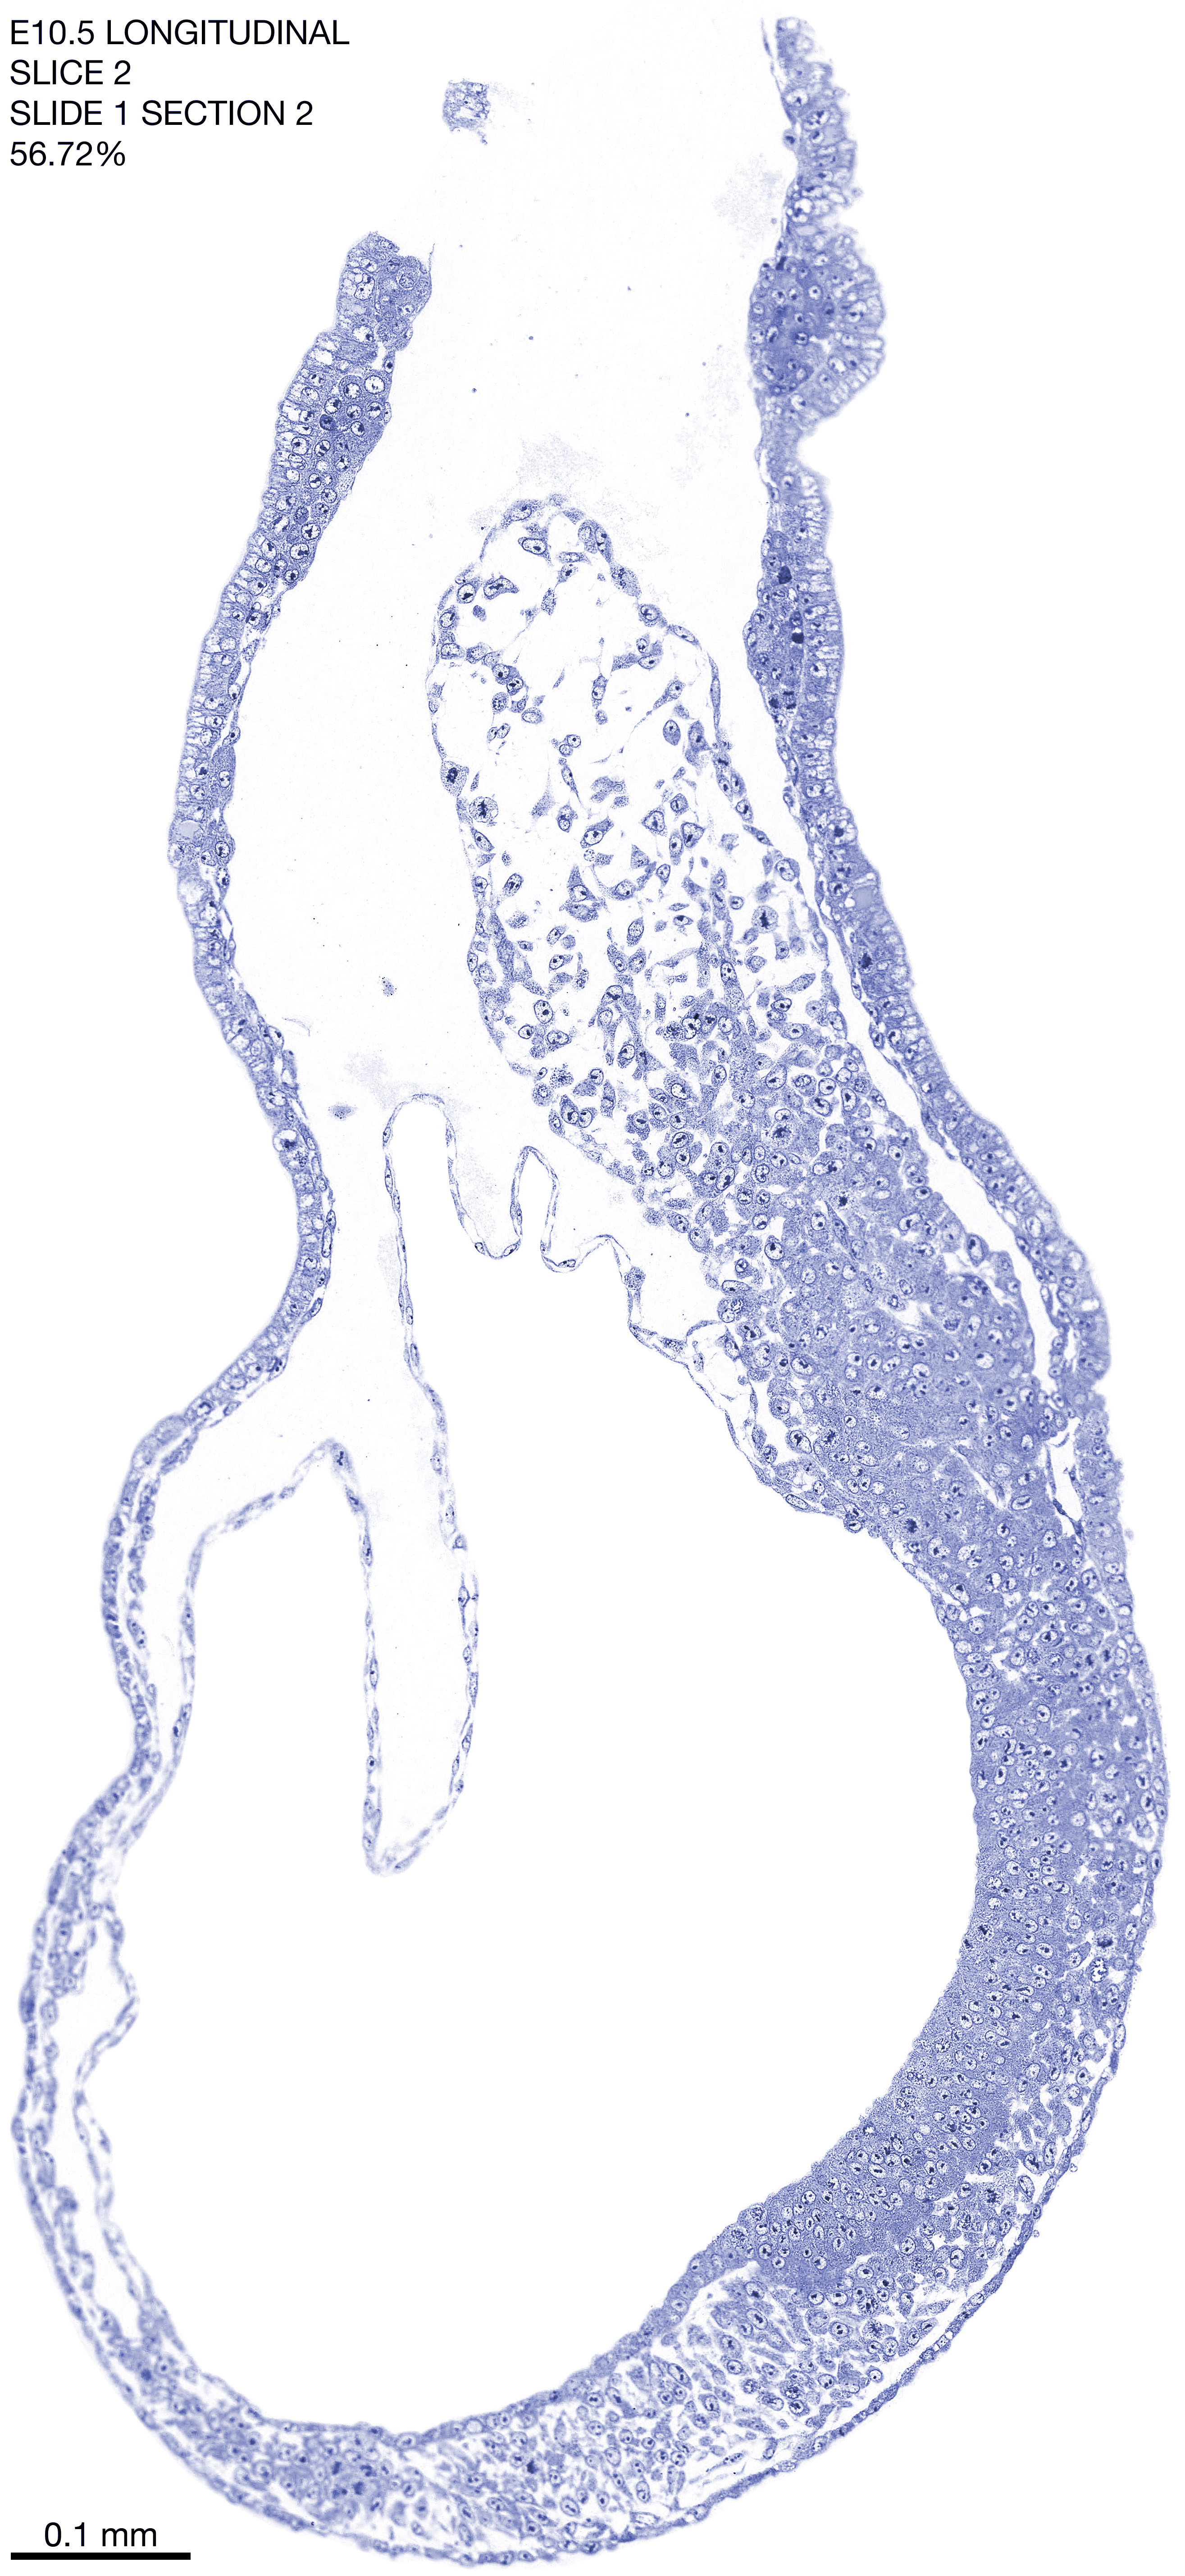

E10.5 Longitudianal Archive This page contains jpg files of ALL SLICES (each 3µm thick) that were scanned of the E10.5 longitudinally cut specimen. Download: Large | High Res Download: Large | High Res Download: Large | High Res Download: Large | High Res Download: Large | High Res Download: Large | High Res Download: Large | High Res Download: Large | High Res Download: Large | High Res Download: Large | High Res Download: Large | High Res Download: Large | High Res Download: Large | High Res Download: Large | High Res Download: Large | High Res Download: Large | High Res Download: Large | High Res Download: Large | High Res Download: Large | High Res Download: Large | High Res Download: Large | High Res Download: Large | High Res Download: Large | High Res Download: Large | High Res Download: Large | High Res Download: Large | High Res Download: Large | High Res Download: Large | High Res Download: Large | High Res Download: Large | High Res Download: Large | High Res Download: Large | High Res Download: Large | High Res Download: Large | High Res Download: Large | High Res Download: Large | High Res Download: Large | High Res Download: Large | High Res Download: Large | High Res Download: Large | High Res Download: Large | High Res Download: Large | High Res Download: Large | High Res Download: Large | High Res Download: Large | High Res Download: Large | High Res Download: Large | High Res Download: Large | High Res Download: Large | High Res Download: Large | High Res Download: Large | High Res Download: Large | High Res Download: Large | High Res Download: Large | High Res Download: Large | High Res Download: Large | High Res Download: Large | High Res Download: Large | High Res